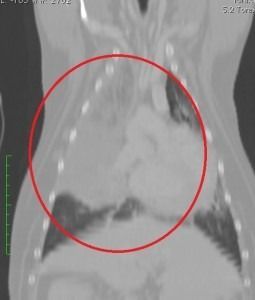

TAC

La tomografía axial computarizada (TAC veterinario), es una técnica de imagen médica que utiliza radiación X, y que permite obtener múltiples imágenes. Facilita el diagnóstico y es una técnica segura para nuestras mascotas.

En Clínica Veterinaria El Parque somos el único centro veterinario con esta tecnología en la provincia de Toledo y alrededores.